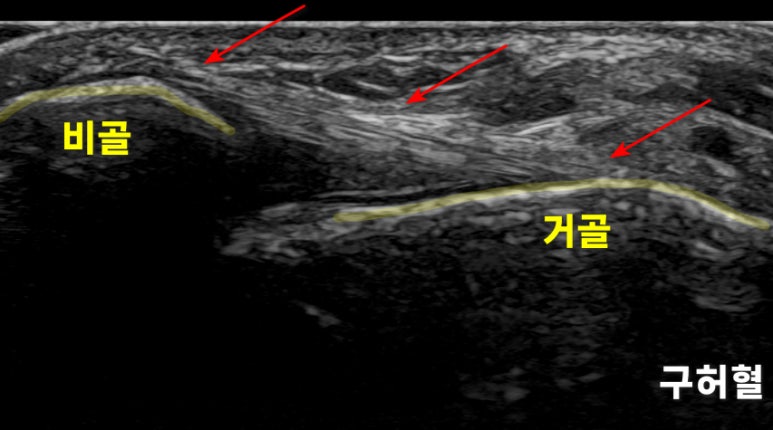

발목 치료의 핵심 혈 자리, 구허혈

위 사진은

바깥쪽 복숭아뼈 전하방에 있는

에서 촬영한

경혈 초음파 영상**입니다.

이 혈자리에서는

비골, 거골이라는 와

두 뼈를 연결하는 가

0.5-1.5cm 깊이에서 나타납니다.

해당 환자분은

통증이 나타나는 구허혈을

초음파로 관찰하였을 때

정상 경혈 모습과는

다른 상태였습니다.

좌측 정상 구허혈, 우측 환자분의 구허혈